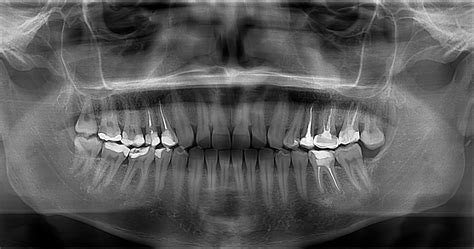

La ortopantomografía es una radiografía en dos dimensiones. La toma de imágenes se realiza a través de un aparato de rayos X. La imagen que se obtiene como resultado es una muestra completa de nuestra dentadura. Esto es muy útil para analizar el estado general de la boca del paciente. Generalmente, es la primera que se hace porque permite detectar infecciones, malformaciones o ausencia de piezas. Sin embargo, el resultado del TAC dental es mucho más preciso y detallado y la radiografía panorámica se queda corta a la hora de realizar algunas intervenciones más complejas.

Las radiografías panorámicas sufren de distorsión debido a que no cumplen con los principios básicos de proyección, lo que resulta en un aumento en el tamaño de la imagen en comparación con las estructuras. Esto limita la precisión de las mediciones realizadas en el examen. Es de gran importancia utilizar tecnologías más precisas y que proporcionen una mayor cantidad de datos a un costo más favorable para el paciente y el odontólogo.

En conclusión, la ortopantomografía es y seguirá siendo una estupenda técnica diagnóstica por su gran ventaja de brindar la anatomía completa del área maxilofacial con baja dosis de radiación para el paciente, aunque claro está que no es recomendable ni adecuado para diagnósticos que requieren un alto nivel de detalle, como en el caso de pérdida ósea temprana o caries incipientes, ya que es necesario visualizar detalles anatómicos pequeños, los cuales son apreciables en las imágenes obtenidas con radiografías intraorales.

La eficacia de cualquier procedimiento diagnóstico se mide por la cantidad de información obtenida a través de su uso. En el caso de la ortopantomografía, existen varios factores muy concretos que pueden afectar de forma negativa la calidad diagnóstica de las imágenes. El principal factor es la posición inadecuada del paciente. Por eso es importante que seas consciente de estos factores y te asegures de supervisar la calidad de tus radiografías panorámicas, utilizando solo aquellas que no presenten errores.